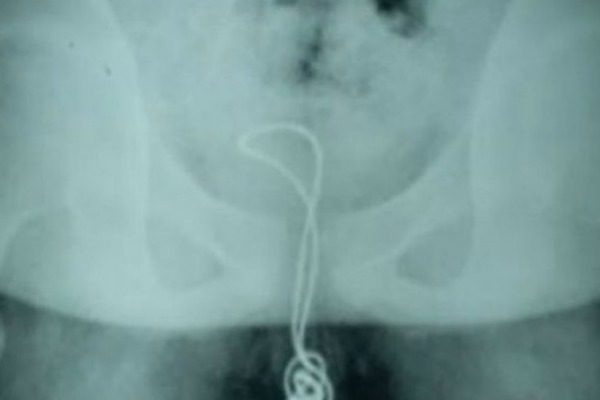

Ο 13χρονος, εξερευνώντας τον εαυτό του, αποφάσισε να δοκιμάσει να βάλει ένα καλώδιο USB στο πέος του, αφού πρώτα έκοψε την μία άκρη το βύσμα.

Μάλιστα κατάφερε να το εισχωρήσει περίπου 20 πόντους, με αποτέλεσμα να φτάσει στην κύστη και να μην μπορεί να το βγάλει.

«Έκοψε την μία άκρη του καλωδίου, την έβαλε στην ουρήθρα του και έφτασε μέχρι την κύστη του. Εκεί μπερδεύτηκε και δημιουργήθηκε κάτι σαν κόμπος, με αποτέλεσμα να μην βγαίνει προς τα έξω και να μείνει κολλημένος», είπε η γιατρός Χου, λίγο μετά την επέμβαση που πραγματοποίησε στην ουροδόχο κύστη.